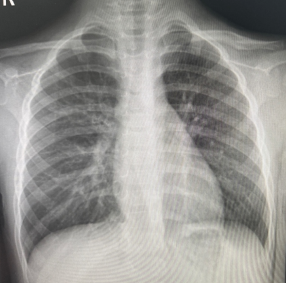

朱某,男,2016-3-15出生,因“跌倒致左肩疼痛伴活动受限2小时”2019年12月12日来我院门诊。检查发现左锁骨区见肿胀、畸形,明显压痛,左肩活动受限。本院X线摄片示:左锁骨骨折,断端明显重叠移位(图1),予以8字绷带外固定制动,定期随访。2020年1月17日复诊述左肩无肿痛,活动基本正常,摄片示:左锁骨骨折,断端对线欠佳,局部明显骨痂形成(图2)。2020年6月8日再次复查摄片示:左锁骨骨折,断端对线可,已骨性愈合(图3)。2023年9月26日再复查摄片示:左锁骨骨折部位已完成塑形,与健侧无明显差异(图4)。

图3